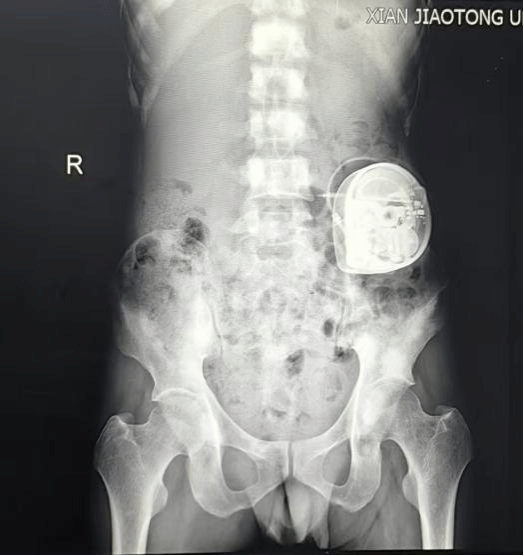

图4 X线透视确认镇痛泵位置良好